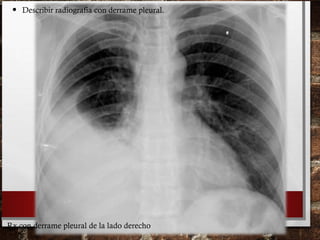

• Describir radiografía con derrame pleural.

Rx con derrame pleural de la lado derecho